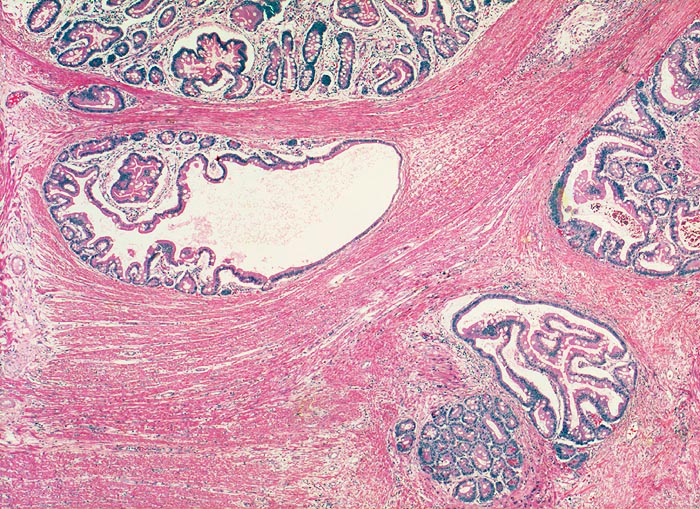

Benigne, in die Muscularis propria verlagerte Drüsenschläuche an der Polypenbasis imitieren ein invasives Karzinom. Die fehlenden Epithelatypien und der normale Epithelaufbau mit begleitender Lamina propria ermöglichen die Unterscheidung von einem Karzinom.

Breitbasiger Polyp von 3cm Durchmesser.

Epithelverlagerungen in die Submukosa und Muscularis propria kommen nur in Dünndarmpolypen vor.